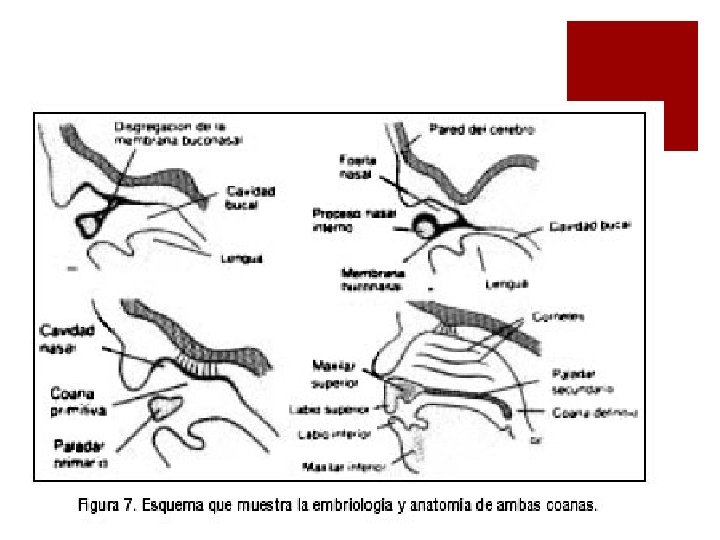

DEFINICION ¡Obstrucción nasal congénita del orificio posterior de las fosas nasales secundario a una alteración del desarrollo embrionario durante la cuarta semana que genera persistencia de la membrana naso-bucal. ¡puede ser: *Unilateral o bilateral. *Membranosa u ósea.

ETIOPATOGENIA